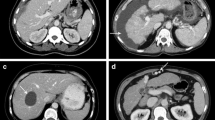

Table 5 and Fig. 3 provide results of subjective image quality evaluation. According to two readers, the median rating of overall image quality was 2 (good) in both groups; however, difference of ratings between groups reached significance towards a higher image quality in group A (p = 0.035). In detail, examinations in group A were exclusively rated as 1 (n = 13/33) or 2 (n = 20/33), whereas ratings in group B were 1 in 6/27, 2 in 16/27, and 3 in 5/27 examinations. Of the five patients in whom the image quality was rated 3, the mean BMI was 44 kg/m2. For both groups, no minor or major motion artifacts were documented.

Figures (A,B) illustrate a high-pitch portal-venous abdominal CT of a 59-year old female patient with acute pain in the upper abdomen (BMI 31 kg/m2, AP + LAT 70 cm; CTDIvol 6.38 mGy, SSDE 6.64 mGy, DLP40cm 222 mGy * cm, ED40cm 3.77 mSv; (A), transversal; (B), coronal), showing both slight swelling of the pancreatic head (*) and diffuse stranding of the adjacent mesenteric fat (arrows). Marked elevation of serum lipase confirmed the suspected diagnosis of acute pancreatitis. Image quality was rated ‚excellent‘. (C,D) show a high-pitch portal-venous abdominal CT of a 41-year old female patient with history of leiomyosarcoma and acute persistent pain in the left lower abdomen (BMI 41 kg/m2, AP + LAT 81 cm; CTDIvol 14.13 mGy, SSDE 12.15 mGy, DLP40cm 587 mGy * cm, ED40cm 10.00 mSv; (C), transversal; (D), coronal). In this CT examination, an extraabdominal mass adjacent to the abdominal muscles on the left was diagnosed, in the sense of an abdominal wall metastasis (arrows in D). The contrast-enhancing tumor had a well-defined morphology, semi-liquid components, and yielded diffuse stranding of the adjacent fatty tissue. The abdominal muscles (* in D) were slightly translocated due to the mass effect, but sharply definable without signs of tumor infiltration. The image quality was rated ‚good‘ in this patient. Figures (E,F) show a high-pitch portal-venous abdominal CT of a 35-year old male patient with acute pain in the right upper abdomen (BMI 47 kg/m2, AP + LAT 86 cm; CTDIvol 17.34 mGy, SSDE 13.53 mGy, DLP40cm 720 mGy * cm, ED40cm 12.24 mSv) (E), transversal; (F), coronal). The CT scan revealed no pathology, particularly no signs of cholecystitis. Overall image quality was rated ‘good’.